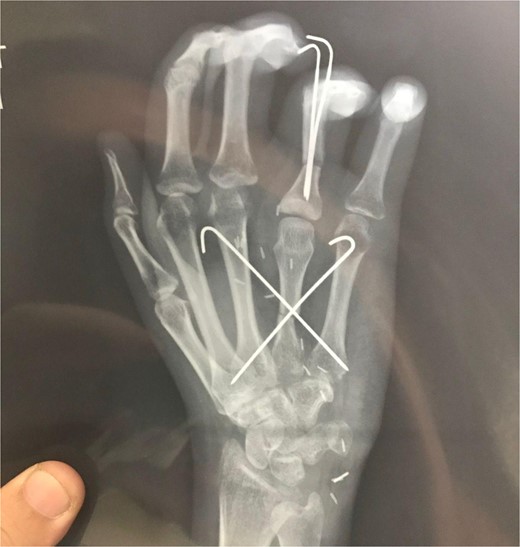

The metatarsal was fixed with the base of the metacarpal using Kirschner wire (K-wire) (Fig. 5A and B). An anastomosis was formed between the ulnar artery and the basilic vein. The artery was anastomosed with the common digital artery of the third web-space and two veins were anastomosed. A 1 deep vein was identified, and the other vein was anastomosed in the superficial venous system on the dorsum of the hand (Fig. 5A and B).

(A) Intraoperative X-ray showing K-wire inserted through the interphalangeal joint crossing the bone flap reaching up to the second metacarpal and another K wire inserted through the interphalangeal joints. (B) After fixation.